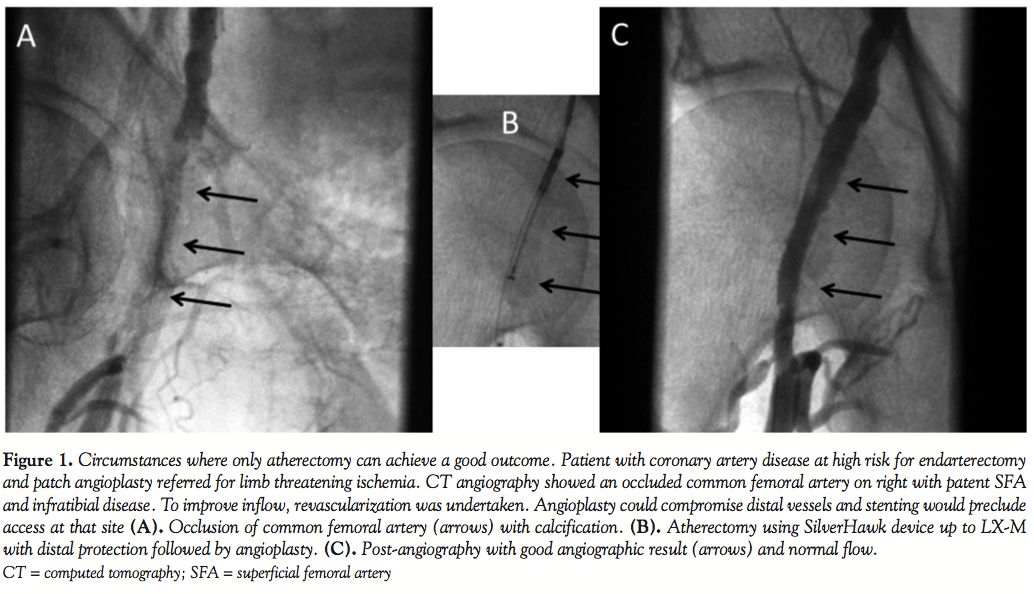

Atherectomy, however, is necessary only for lesions in areas that are not amenable to stenting [such as common femoral artery (Figure 1), bifurcations, contraindications to vascular surgery], and can only be universally recommended after well-designed, adequately powered, randomized, controlled trials are carried out to demonstrate its efficacy, safety, and cost-effectiveness. Furthermore, the true mechanism of plaque removal with the various atherectomy devices needs to be better elucidated through larger trials. Although both the Jetstream and Diamondback devices are supposed to perform atherectomy and plaque removal, a recent study of 1029 patients reported that both JetStream and Diamondback 360 devices have a higher rate of distal embolization.9 Unless these studies are performed or if its effectiveness is not proven superior to angioplasty/stenting, peripheral atherectomy will be relegated to “niche” applications as it did in the coronary circulation. The need for larger sheath size, distal embolization, time requirements, and cost limit its use unless its superiority is proven beyond doubt. It is surprising that tens of thousands of atherectomy procedures are performed annually with little data to support their use over angioplasty/stenting.